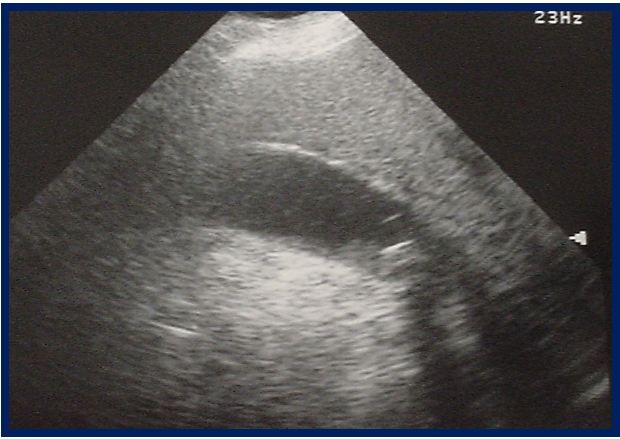

Figure 1. ED ultrasound abdomen. Click to enlarge.

Blood work including a CBC, metabolic panel, LFTs, UA, and pregnancy test are all completely normal except for 79% PMN’s on the differential. An abdominal ultrasound is performed and one of the images is shown in Figure 1 (please click on image to enarlge).

Question 1. What is notable on this ultrasound image?